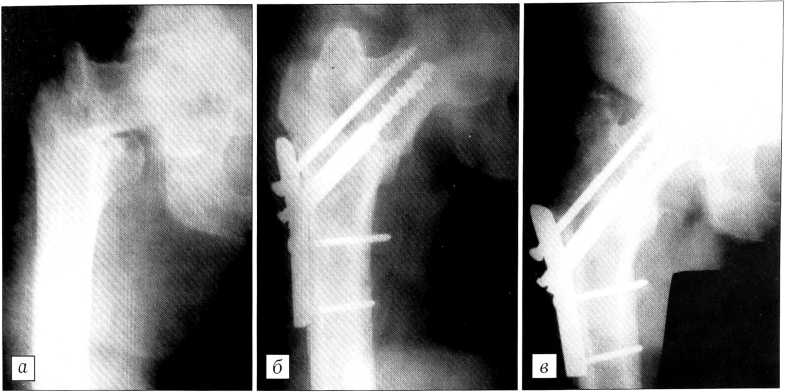

Больная М.,69 лет, поступила 03.12.99 через 2 ч после травмы (падение на улице). Диагноз: закрытый подвертельный перелом правой бедренной кости со смещением отломков 31 АЗ.2. Сопутствующий диагноз: ишемическая болезнь сердца; атеросклеротический кардиосклероз Н2; атеросклероз сосудов головного мозга; гипертоническая болезнь III стадии. 07.12.99 произведен остеосинтез правого бедра компрессирующим устройством. Больная выписана из отделения через 18 сут. Спустя 4 мес после операции: полное восстановление функции оперированной конечности, пациентка полностью обслуживает себя (рис. 6).

Рис. 6. Рентгенограммы правого тазобедренного сустава больной М. 69 лет. а - при поступлении: подвертельный перелом правой бедренной кости со смещением отломков, тип 31 АЗ.2; б — после остеосинтеза.